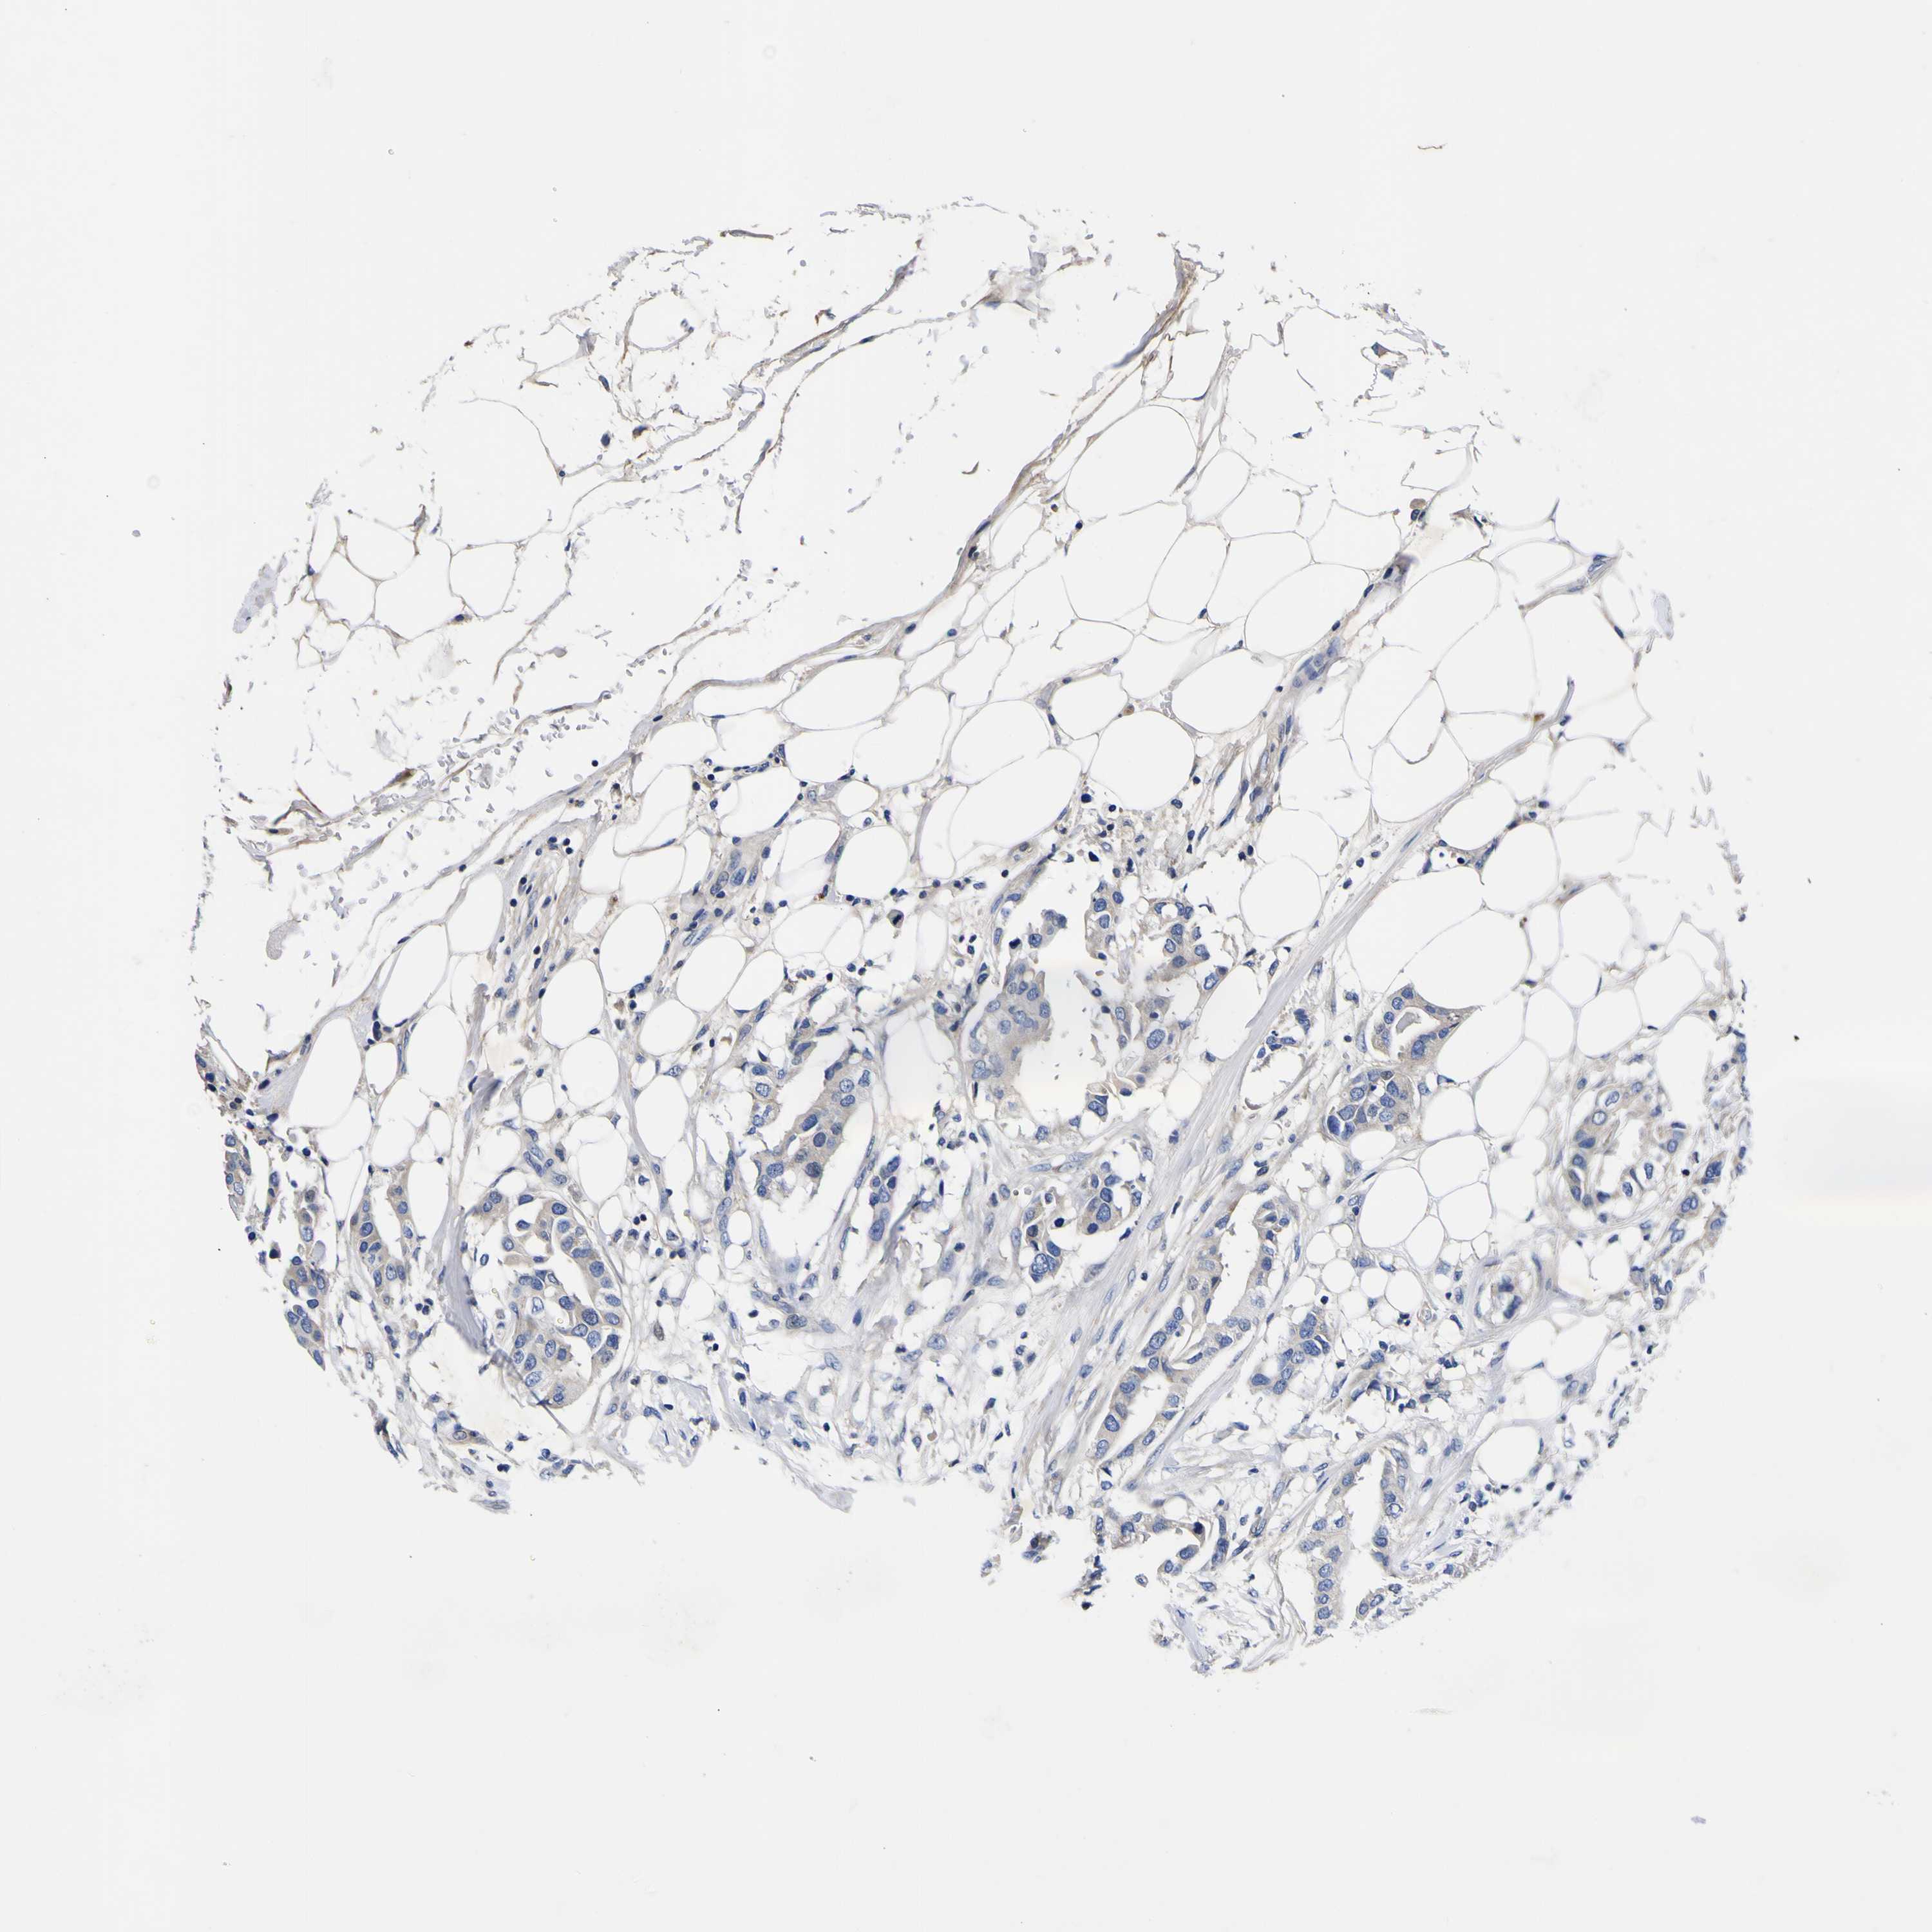

CANCER BREAST CANCER Show tissue menu

BRCA TCGA BRCA VALIDATION PROTEIN EXPRESSION